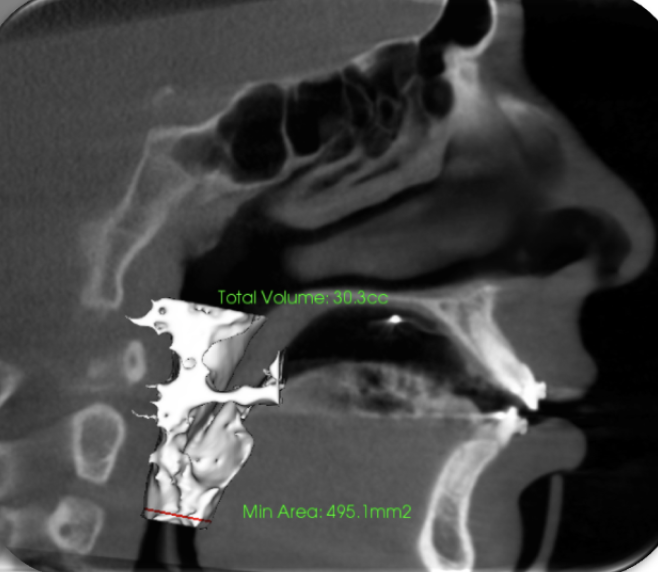

Expansion and lower jaw andvancement opened his airway from 11 to 3o CC.

Before

After

This patient was treated without extractions!